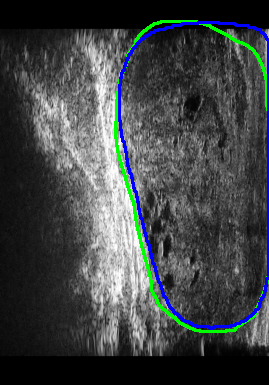

Figure 4 presents the performance evaluation of three loss functions—Adaptive Focal Loss, AG-BCE Loss, and PyTorch Focal Loss—on three test images. Each row in the figure corresponds to the segmentation results of one loss function, while the columns represent the respective test images. A legend at the top provides the color coding for the ground truth and the outputs of the three loss functions, allowing for a direct visual comparison of their performance.

The visual analysis of segmentation results, illustrated in Figure 5, demonstrates that Adaptive Focal Loss consistently achieves more accurate segmentation, particularly in regions with low contrast, high noise, or complex anatomical variations, closely aligning with the ground truth.

Further comparisons of Test 17, Test 18, and Test 19, shown in Figure 6, underscore the effectiveness of the Adaptive Focal Loss in handling challenging prostate boundary regions.

1.

Test Image 17: The Adaptive Focal Loss performed exceptionally well in the upper left region, which presented significant anatomical deformation, making segmentation particularly difficult. In contrast, AG-BCE produced an overly smooth boundary, while PyTorch Focal Loss severely under-segmented the area.

-

2.

Test Image 18: This image highlighted challenges in the lower prostate boundary caused by artifacts and low contrast. The Adaptive Focal Loss accurately delineated the boundary, whereas AG-BCE exhibited boundary shifts and PyTorch Focal Loss resulted in under-segmentation.

3.

Test Image 19: The Adaptive Focal Loss again outperformed the other methods, especially in the upper right region, where tissue density variations blurred the boundary. AG-BCE over-segmented this region, and PyTorch Focal Loss produced inconsistent results, with instances of both under- and over-segmentation.